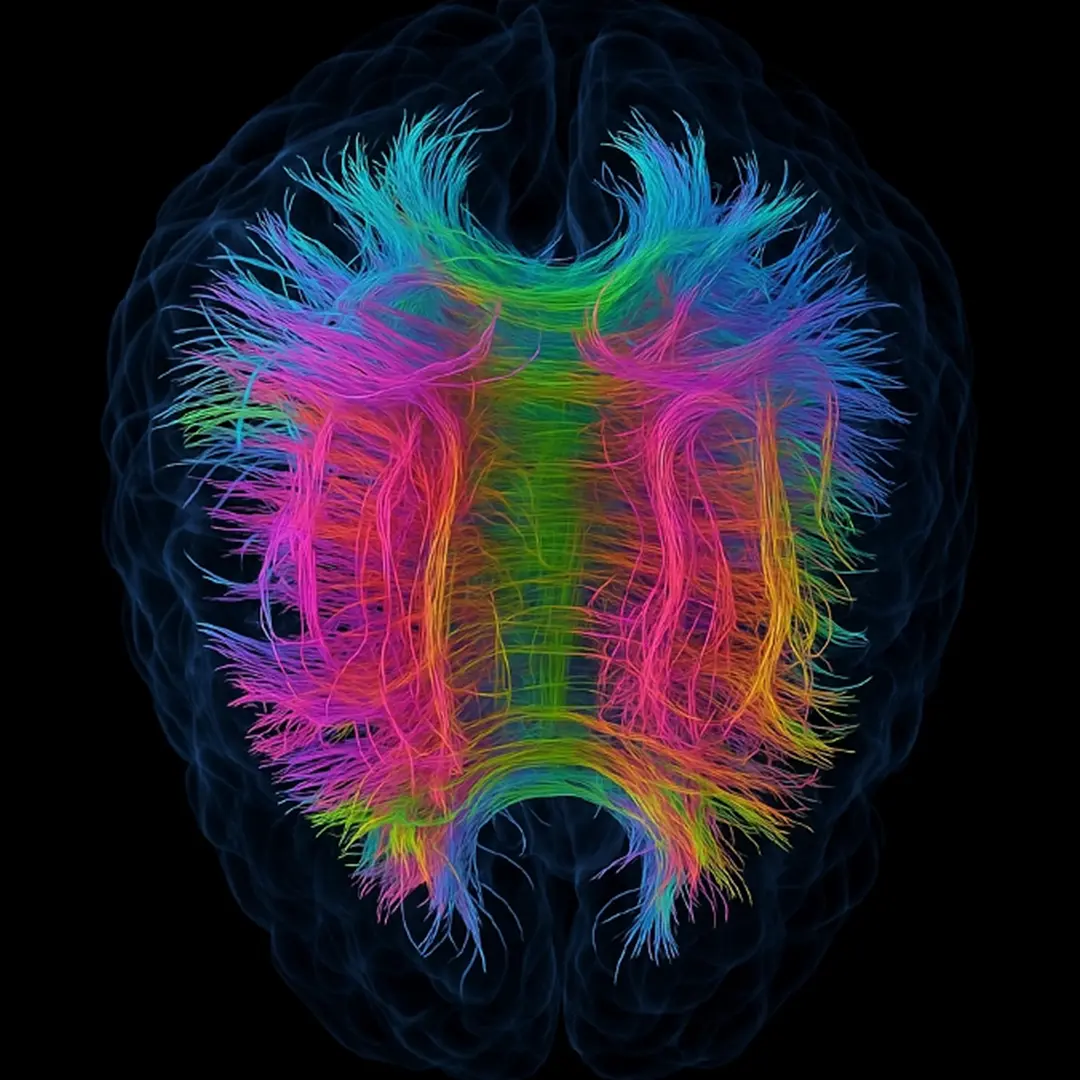

DIFFUSION TENSOR IMAGING (dti)

WHAT IS A DTI EXAM?

Diffusion Tensor Imaging (DTI) is one of the most advanced tools available for detecting traumatic brain injuries that traditional MRI and CT scans often overlook. By mapping white matter pathways, DTI uncovers diffuse axonal injury (DAI), even after mild trauma.

DTI delivers deeper brain visualization and objective evidence of injury, empowering earlier detection, clearer answers, and more confident clinical decisions.

WHY DTI STUDIES ARE IMPORTANT

Diffusion Tensor Imaging (DTI) is highlighted as a superior diagnostic tool for identifying brain issues that standard imaging might overlook.